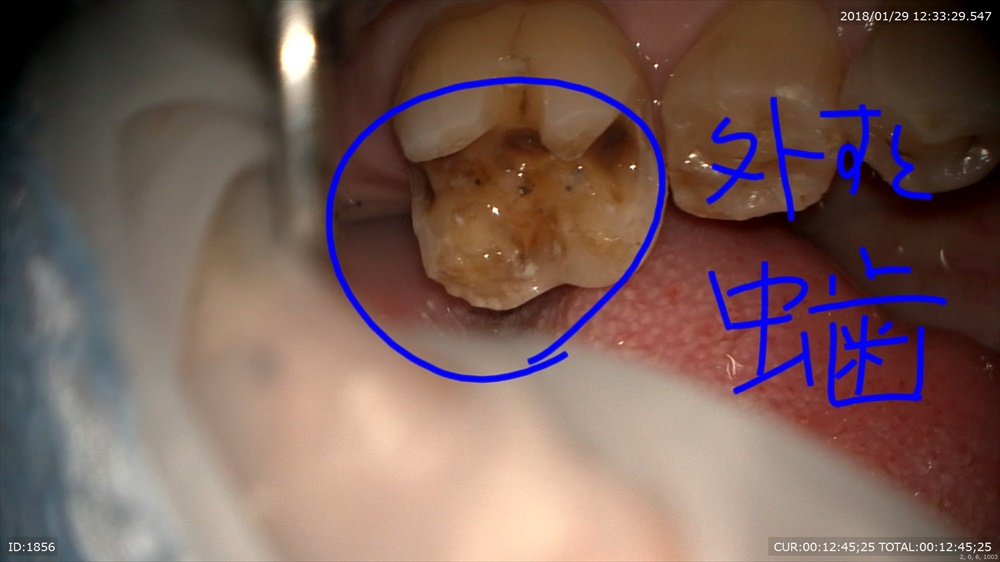

次はむし歯 銀歯の後ろが欠けていました。

外すと 銀歯むし歯

綺麗にして 検知液で確認!!